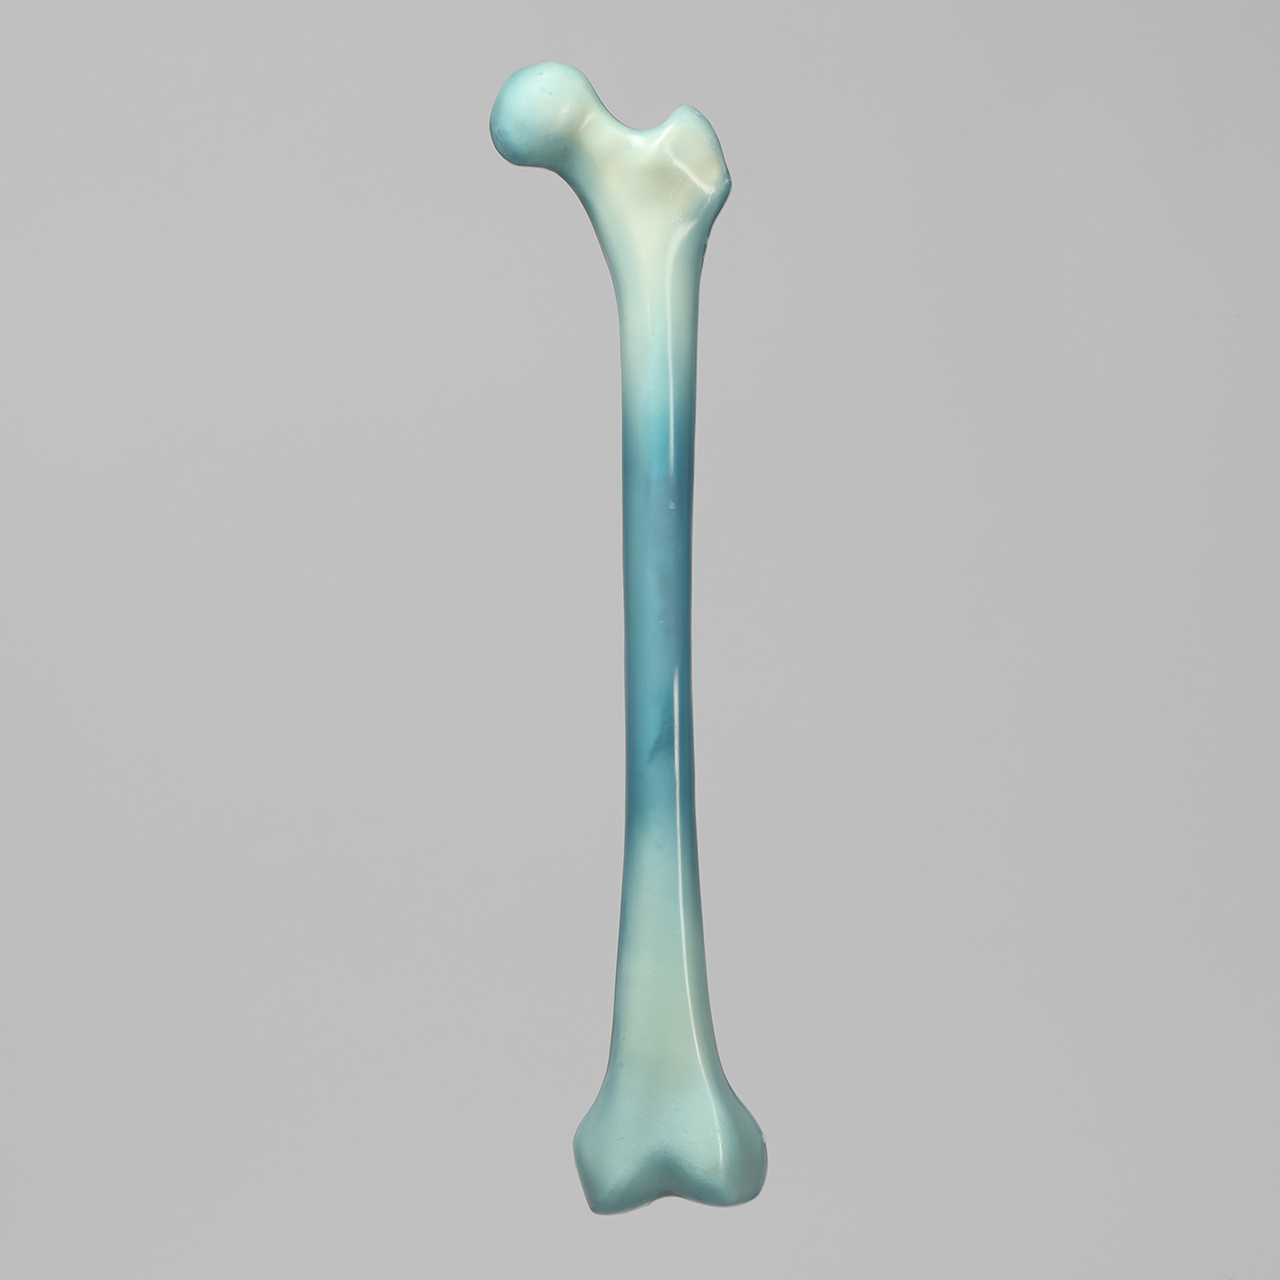

人工骨骨盆模型3415

人工骨模型,完整男性骨盆,absolute™ 第四代,17 PCF 实心泡沫芯,大号

用于力学测试的完整男性骨盆

我们的 absolute™ 骨模型 精确模拟人体骨骼的结构与力学特性,能够帮助科研人员和医疗器械企业在开发与审批过程中,轻松且经济地再现载荷与运动场景。该模型特别适用于生物力学研究、医疗器械测试及教学演示。

| 解剖部位 (Anatomy) | 骨盆 – 完整 |

| 模型类型 (Model Type) | absolute™ 骨模型 |

| 材料 (Material) | absolute™ |

| 尺寸 (Size) | 大号 |